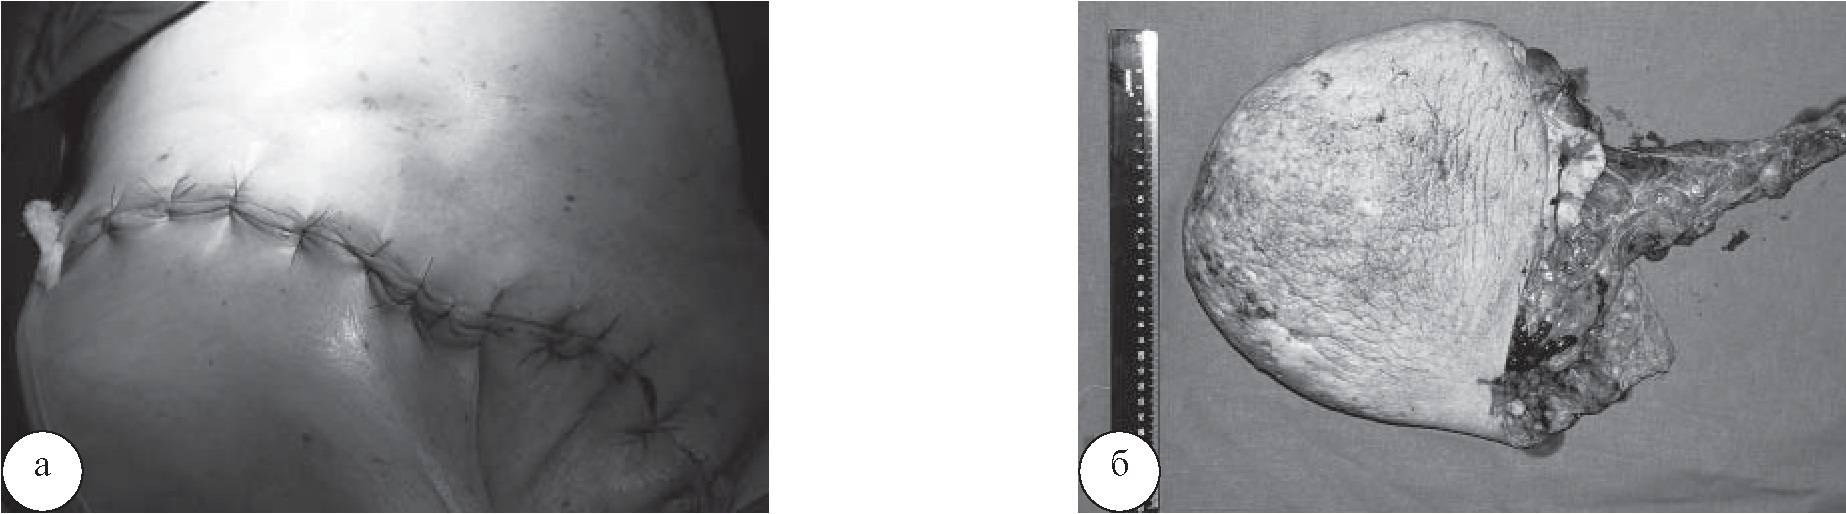

При поступлении пациентки состояние удовлетворительное. Температура тела 36,8оС. Кожный покров и видимые слизистые обычного цвета. Дыхание жесткое, проводилось во все отделы. Хрипы не выслушивались. Частота дыхательных движений 14 в минуту. Язык влажный. Живот при пальпации мягкий, безболезненный. Мочеиспускание свободное, диурез достаточный. Стул ежедневный, оформленный. В правой паховой области – грыжевое выпячивание размерами 44×23 см, опускающееся до уровня правого коленного сустава. Кожа в области грыжи гипертрофирована, с участками мацерации размерами от 0,5 до 2 см (рис. 1). При пальпации выпячивание мягко-эластичной консистенции, безболезненное, в брюшную полость невправимое. Симптом «кашлевого толчка» положительный. В результате обследования данных за ущемление грыжи не получено. Показаний к срочной операции не было.

Рис. 1. Общий вид больной: а – спереди; б – сбоку

Через двое суток нахождения пациентки в отделении хирургической реанимации ее состояние было стабильным, соответствовало средней степени тяжести. Явлений сердечно-сосудистой и дыхательной недостаточности обнаружено не было. Болевой синдром купирован. Сохранялась интраабдоминальная гипертензия первой степени. Для дальнейшего лечения пациентка переведена в хирургическое отделение, где ей проводилась инфузионная, антибактериальная, противовоспалительная, антикоагулянтная, анальгезирующая терапия, выполнялась дыхательная гимнастика. На вторые сутки после операции пациентка самостоятельно передвигалась по отделению. Послеоперационный период протекал гладко, на 13-е сутки после операции пациентке сняли все швы и выписали из стационара. В настоящее время пациентка ведет активный образ жизни. Общий вид больной через 3 месяца после операции представлен на рисунке 5.

Рис. 5. Вид послеоперационной раны через 3 месяца после операции